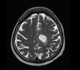

Gliomas are classified according to the specific type of cells involved, as follows:

• Ependymoma - This tumor arises from the ependymal cells. which are found in the brain ventricles and spinal cord.

• Astrocytoma - This tumor involves the astrocytes, cells that transport nutrients, as well as providing structural support to neurons.

• Oligodendroglioma - Here, cells called oligodendrocytes are involved. These cells provide insulation in the form of myelin.

• Mixed gliomas - These are tumors that contain a combination of cell types such as an oligoastrocytoma, for example.

Gliomas are also classified according to their grade. Low-grade gliomas are usually slow growing, non-malignant and are associated with a better outcome over high-grade gliomas, which are malignant and more aggressive.